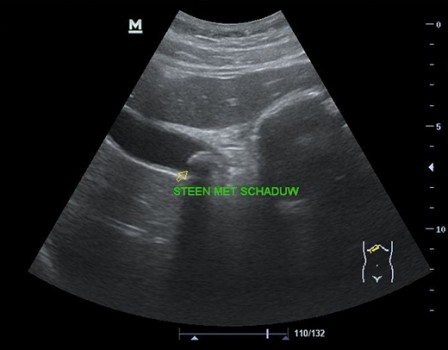

Een 37-jarige vrouw komt met bovenbuikklachten op het spreekuur. In de anamnese staat 3 keer aanvalsgewijze bovenbuikklachten die doortrekken naar de rug. Uit de echografie tijdens hetzelfde consult blijkt dat ze galstenen heeft [figuur 2]. Mevrouw gaat naar huis met instructies, een recept diclofenac-zetpillen voor eventuele koliekpijnen en een verwijzing voor de chirurg. Een maand later maakt een laparoscopische cholecystectomie een einde aan haar galsteenlijden.

Figuur 2 | Galsteen met slagschaduw